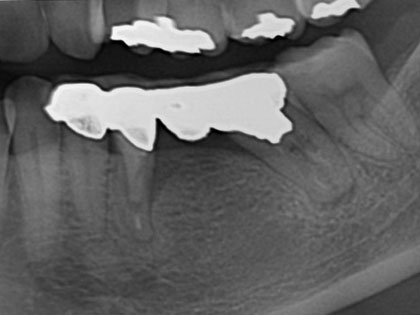

• 治療中の写真がこちら

• インプラント治療中3

• 左下5の骨造成、インプラント

• 左下6のインプラント

• 抜歯時に骨造成を同時に行い、そこから4か月後にインプラントを埋入しました。